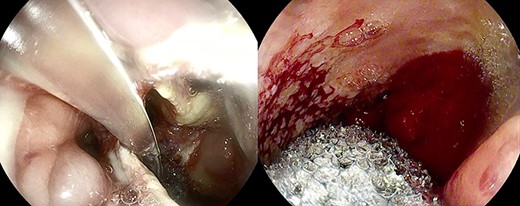

Healthy-appearing granulation tissue and progressive reduction of leak and cavity size.

The patient underwent 14 treatment sessions over 35 days. The leak and the cavity size progressively improved with the development of healthy-appearing granulation tissue s (Fig. 3). Inflammatory indexes and clinical conditions similarly improved. The endoscopic findings were confirmed by CT scans. Complications were not observed.